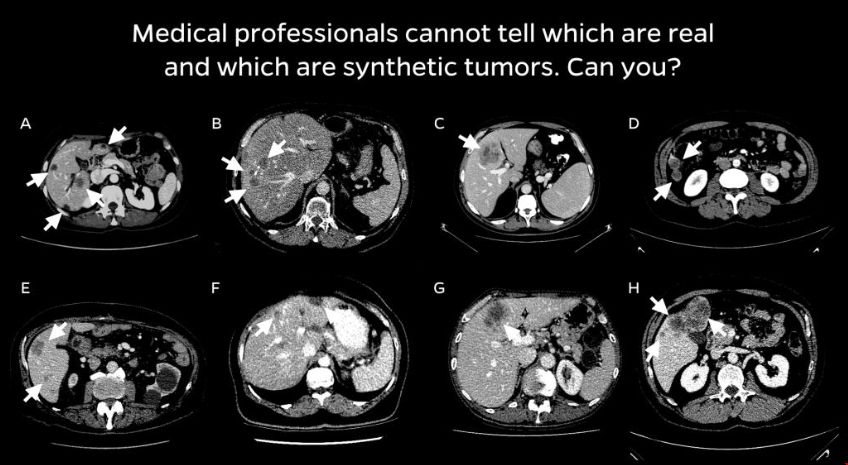

該團(tuán)隊(duì)與放射科醫(yī)生合作,設(shè)計(jì)了一種四步合成現(xiàn)實(shí)腫瘤的方法。首先,他們?yōu)槿嗽炷[瘤選擇了避免與周圍血管碰撞的位置。接下來,他們添加了隨機(jī)的“噪聲”模式,這樣他們就可以生成在真實(shí)腫瘤上發(fā)現(xiàn)的不規(guī)則紋理,并生成反映真實(shí)腫瘤不同輪廓的形狀。最后,他們模擬了腫瘤擠壓周圍環(huán)境的傾向,這改變了它們的外觀。研究人員說,合成的腫瘤是超現(xiàn)實(shí)的,并且通過了視覺圖靈測(cè)試——也就是說,即使是醫(yī)學(xué)專業(yè)人員在視覺檢查中也會(huì)把它們和真實(shí)的腫瘤混淆。